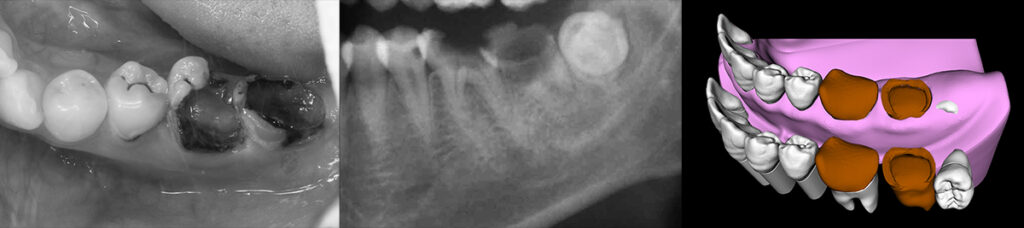

年配者と若者世代では歯科再建治療に対するアプローチはまったく異なる。 生存年数や活動年数が中高年世代と20代の世代では30年以上の実質差があり、長期的な戦略としてはエナメル質の保存、歯髄の保存が最優先し、生体としての自己再生能を維持すべき治療が推奨される。 以下の症例は治療開始時24歳で下顎第一大臼歯は歯冠崩壊が顕著であるも、歯根部はかろうじてカリエス進行から免れるが、第二大臼歯は完全に歯根も腐食して保存不能。

ムシバを放置したため歯冠崩壊顕著の大臼歯